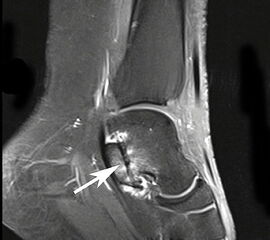

MRT

Unterbrechung des Retinakulums als indirektes Zeichen einer traumatischen Peronealsehnenluxation im MRT.

Abbildung 6

Neben der klinischen Untersuchung besitzt in der Diagnostik von Sehnenpathologie das MRT mit Kontrastmittel einen hohen Stellenwert 8910. Kontrastmittelaufnahme in die Sehne ist immer als Hinweis auf einen Riss zu werten. Weiterhin ist Flüssigkeit im Sehnengleitlager oder die Aufnahme von Kontrastmittel in das Sehnengleitgewebe ein indirektes Zeichen einer Sehnenpathologie.